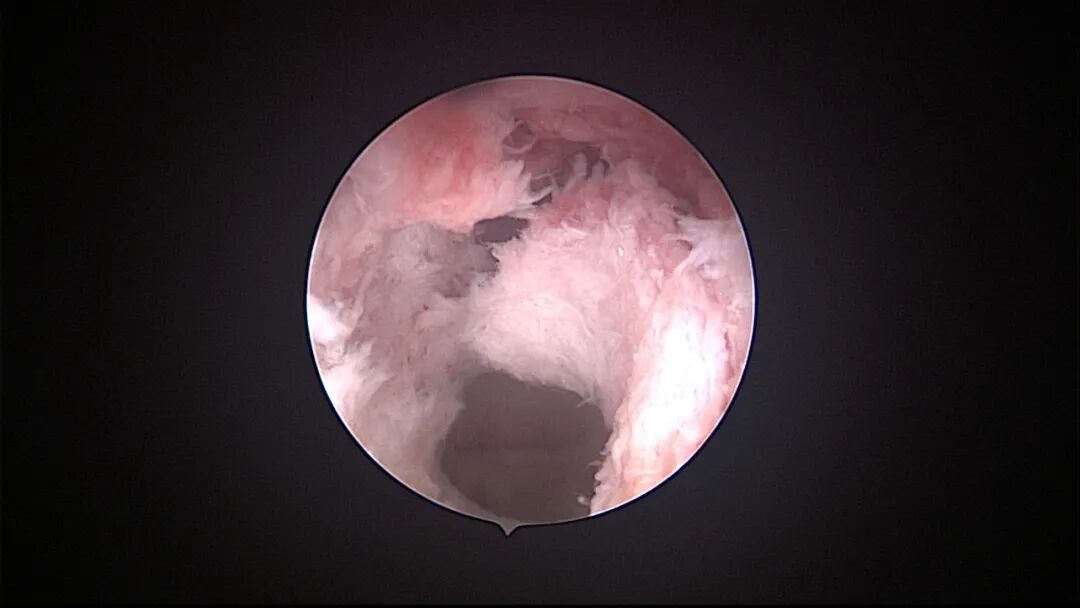

6例外院取环失败,子宫假道

为了宫腔镜手术平稳顺利进行,宫腔镜术前准备及安全评估非常重要,尤其是充分的安全评估能有效减少并发症的发生。阴道情况:萎缩、纵膈、斜膈等可能导致扩阴器置入困难。肥胖病人、高个子病人阴道很深,宫颈可能难以暴露;宫颈情况:绝经后病人宫颈萎缩、狭窄、坚硬,加之穹隆展平,宫颈难以夹持、难以扩张;宫颈管弯曲、宫颈肌瘤、巨大息肉、粘膜皱襞隐窝、巨大纳囊等,可能阻挡宫腔镜进入宫腔;子宫情况:子宫萎缩,宫腔狭小,子宫极度前屈、后屈、侧屈等极端位置常常导致宫腔镜置入困难;既往盆腔手术史:子宫与盆腔器官粘连可能导致子宫极端位置,或者宫深超出预期。近期手术情况:外院取环失败、人流不全、宫腔探查或试图分粘中途放弃等病人,子宫可能存在假道、穿孔或盆腔积血等损伤。这类病人评估重点:前次手术医院级别、既往分娩情况、安环多少年、月经情况、闭经或绝经时间、手术日期、手术时间长短、是否麻醉、术后有无腹痛、有无阴道出血、B超情况、腹部平片、血糖血压等。宫腔镜术前需再次复查B超,手术医生到B超室了解子宫位置、大小、有无损伤、节育环种类及位置、是否嵌顿、盆腔有无积液等细节。